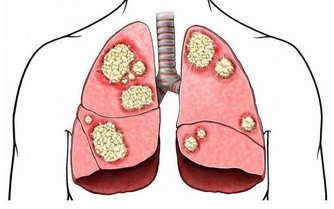

隨著生活水平的提高,人們的飲食條件越來越好,但很多人卻不注意飲食,造成了腸癌的發病機率上升。實際上,腸癌的發生跟生活方式有很大的關係,而且男性的發病機率明顯高於女性。在臨床上,腸癌在早期時症狀不明顯,即使有症狀也會被人忽視,只是感覺到身體不適,容易消化不良。

一般來說,以下異常表現的出現就是腸癌的早期症狀:

在按壓腹部時,患者會明顯的感覺疼痛,而且也會有包塊的存在。這是腫瘤跟周圍的組織粘在一起形成的腫塊,而且這些腫塊會活動。在檢查B超時,會發現腫塊的大小不規則,尤其是到了晚期,腫塊會不斷增大,變得不再活動。

總而言之,腸癌對人體健康的影響是很大的,屬於惡性腫瘤。若平時感覺到身體不適,經常的出現便血,必須要合理的進行檢查。如果出現腸癌,也不要氣餒,不要放棄治療。在早期時,疾病可以有效控制,患者需選擇適合的治療方法,有效的緩解疼痛。千萬不要坐以待斃,放棄治療。